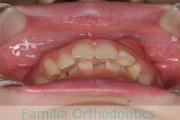

No.22V-498

- 上顎前突

- 側方偏位

- 年齢:

- 26歳

- 性別:

- 女性

- 抜歯部位

- 上:

- 44

- 下:

- 8|58

上の前歯が出ているのと下の前歯のでこぼこを治したいということで来院されました。左右のズレがあるので、上顎を左右から、下顎は左下のみ小臼歯を抜歯して、アンカースクリューを併用したマルチブラケット法にて治療を行いました。2年強、25回程度の通院が必要でした。

前歯の移動量が多いケースとなりますので、歯根吸収や歯肉退縮のリスクが高めです。